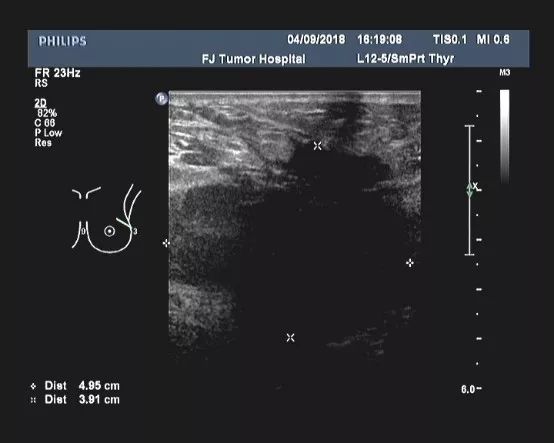

女性患者,30岁,未绝经,家族史不详(患者本人为领养)。于2018-01发现左乳肿块,当地医院乳腺MRI示:左侧乳腺外上象限可见5*7cm大小团块状影,左侧腋下可见多个肿大的淋巴结。B超提示:左乳外上象限探及一低回声区,大小约4.9cm×3.9cm,边缘不规则,可见成角、毛刺,内部回声不均;左腋上中下组探及数个低回声,大者约2.2cm×1.8cm,边界尚清,类圆形,皮髓质分界不清,皮质不规则增厚,淋巴结门消失;右乳及右腋窝未见异常。 PET-CT结果:1、考虑左乳外上象限癌累及胸大、小肌。 2、考虑左锁骨区、左胸大肌及胸小肌深面、左腋窝多发淋巴结转移。

▎疗效评估: B超(2018-04):左乳外上象限探及一低回声区,大小约4.9cm×3.9cm,边缘不规则,可见成角、毛刺,内部回声不均;左腋中下组探及数个低回声,大者约2.5cm×1.6cm,边界尚清,类圆形,皮髓质分界不清,皮质不规则增厚,淋巴结门消失;右乳及右腋窝未见异常。